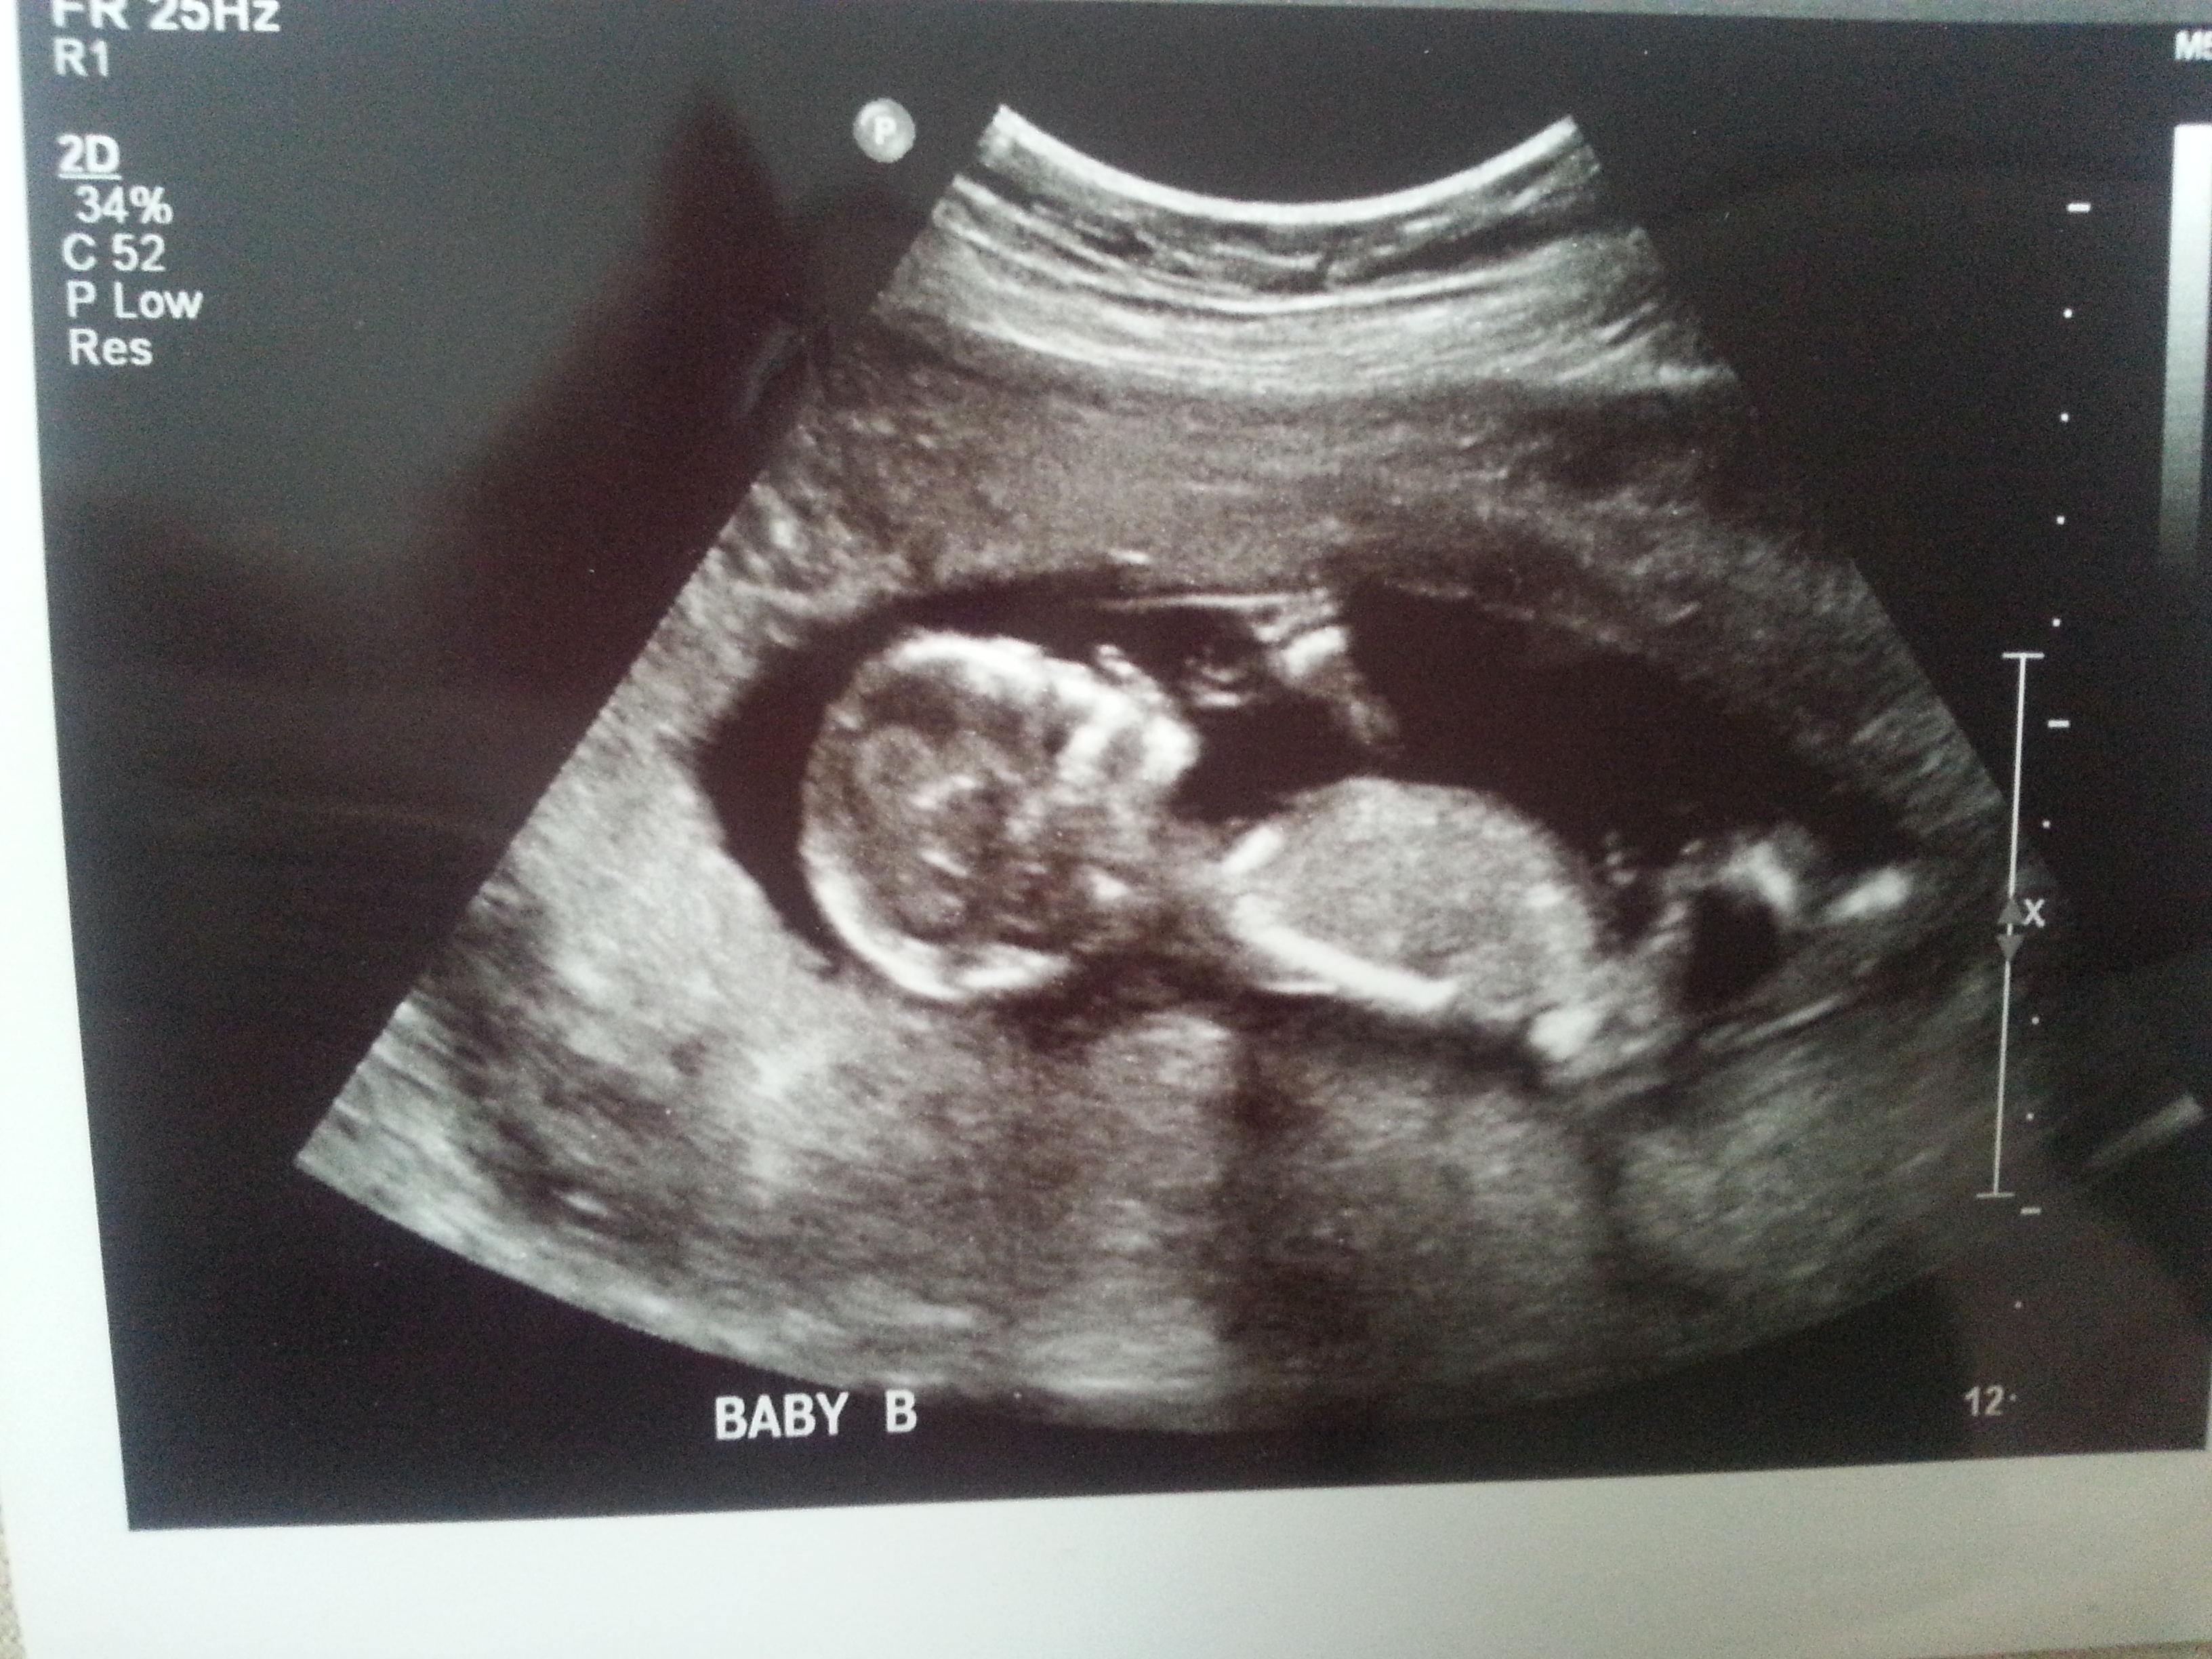

I was 12weeks 6 days and measuring 13weeks 3 days.

Maybe boy/girl. Not the best shots though!

I think I'm seeing a very boyish nub for baby B. Baby A not as sure. I hope that's your girl! Congrats and good luck!

On your second pic of baby B I'm looking at the little line between the legs that's almost sticking straight up.... very boyish "angle of the dangle".